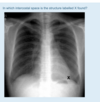

22

1

Apex

23

2.

RV

24

3

RA

25

4

Ascending aorta

26

5

LA

27

6

Descending aorta

28

7

LV

29

8

oesphagus

30

trachea

31

2

aortic knuckle/knob

32

33

34